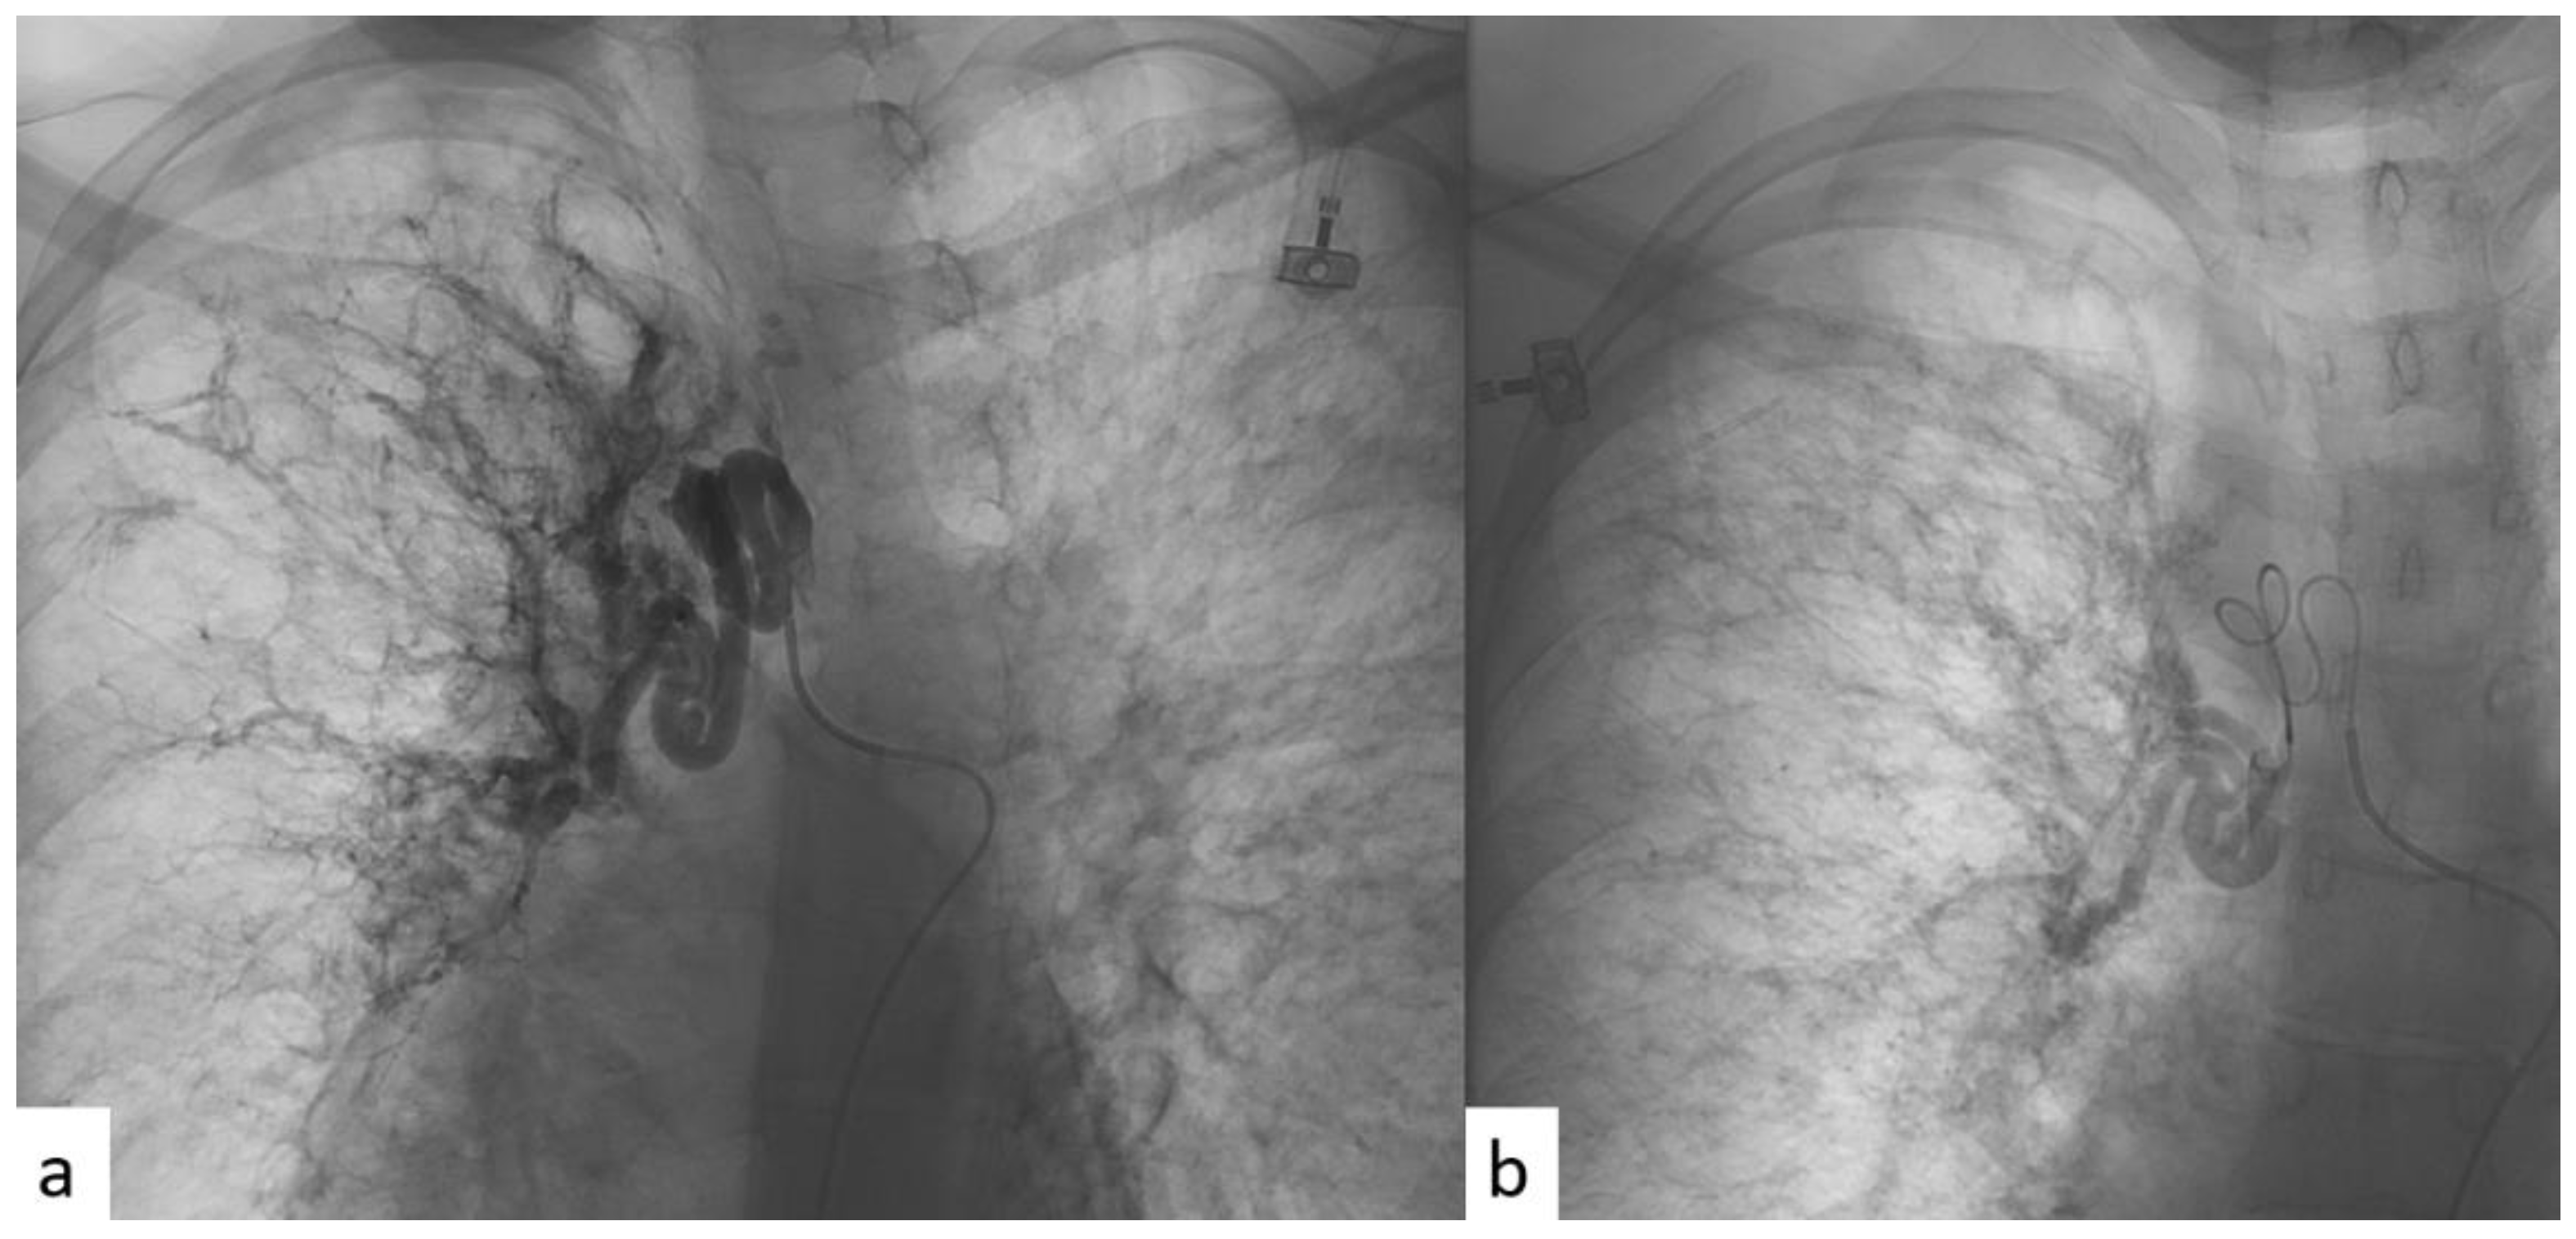

| Procedures | ID Pz. | Vessel Type Treated with BAE | Caliber of Treated Vessel (mm) Pre-Procedure CT | Untreated Vessel Size (mm) Pre-Procedure CT | ∆ Significant Caliber between Left and Right? | Arterial Vessel Studied in Diagnostic Angiography |

| 1 | 1 | Left | 5 | 2 | Yes | Bronchial left |

| 2 | 1 | Left | 5 | 3 | Yes | Bronchial left |

| 3 | 2 | Right | 6 | 2 | Yes | Bronchial right |

| 4 | 2 | Left + Right | 7.5 | 3.5 | Yes | Bronchial right and left * |

| 5 | 3 | Right | 6 | 3.5 | Yes | Bronchial right |

| 6 | 4 | Right | 7 | 6 | No | Bronchial right and left |

| 7 | 5 | Right | 3.5 | 3.5 | No | Bronchial right and left |

| 8 | 6 | Right | 8 | 5 | Yes | Bronchial right |

| 9 | 7 | Right | 5 | 2 | Yes | Bronchial right |

| 10 | 7 | Right | 5 | 2 | Yes | Bronchial right and left |

| 11 | 7 | Right | 5 | 2 | Yes | Bronchial right |

| 12 | 8 | Right | 3 | 2 | No | Bronchial right and left |

| 13 | 8 | Right | 4 | 2 | No | Bronchial right and left * |

| 14 | 9 | Left | 8 | 7 | No | Bronchial left * |

| 15 | 10 | Right | 7 | 1 | Yes | Bronchial right |

| 16 | 10 | Right | 7 | 1 | Yes | Bronchial right |

| 17 | 11 | Right | 5 | 3 | No | Bronchial right and left |

| 18 | 12 | Left | 7 | 4.5 | Yes | Mammary left |

| 19 | 13 | Right | 3.5 | 0.5 | Yes | Bronchial right |